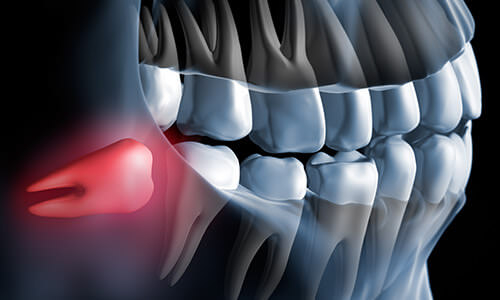

親知らずとは、一番奥に、そして一番最後に生える歯(下顎第三大臼歯および上顎第三大臼歯)のことを言います。18歳〜20歳位で生えることが多い歯です。最近では、食事がやわらかくなり、噛む回数減少のため、顎が小さくなる傾向になって生えない人の方が多いです。

結果、親知らずが生えてくるスペースが不足してしまい、水平に生えたり、傾斜して生えたりし、痛み・腫れ・歯列不正など様々なトラブルを引き起こす原因となるため、抜歯が必要となるケースも多いです。

また、斜めに生えているなどの場合、歯茎や顎の骨を圧迫して痛みを与えたり、歯並びにも影響し身体のバランスが崩れることもあります。